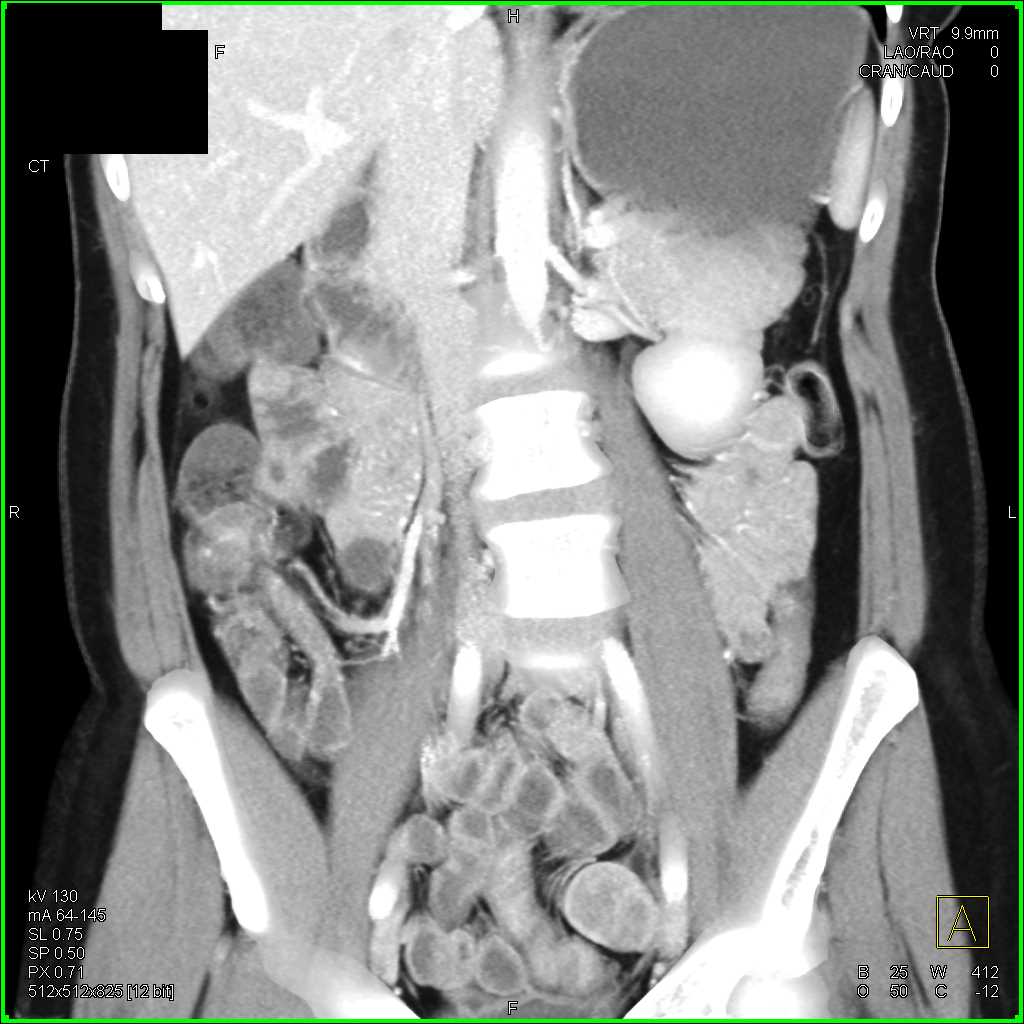

Crohns Disease Terminal Ileum